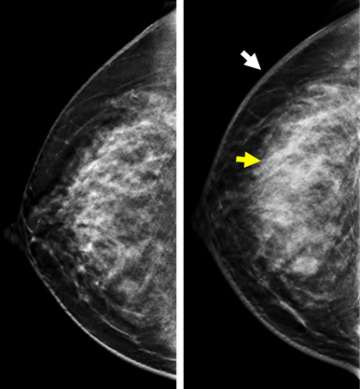

Mammography/ DBT

Typical mammographic findings include global or focal asymmetry, skin thickening, trabecular thickening, diffuse increase in breast density, and stromal coarsening (Figure 1). In addition, dense and irregular axillary adenopathy are seen in approximately one half of the cases. Multiple masses and pleomorphic calcifications are uncommonly described features.